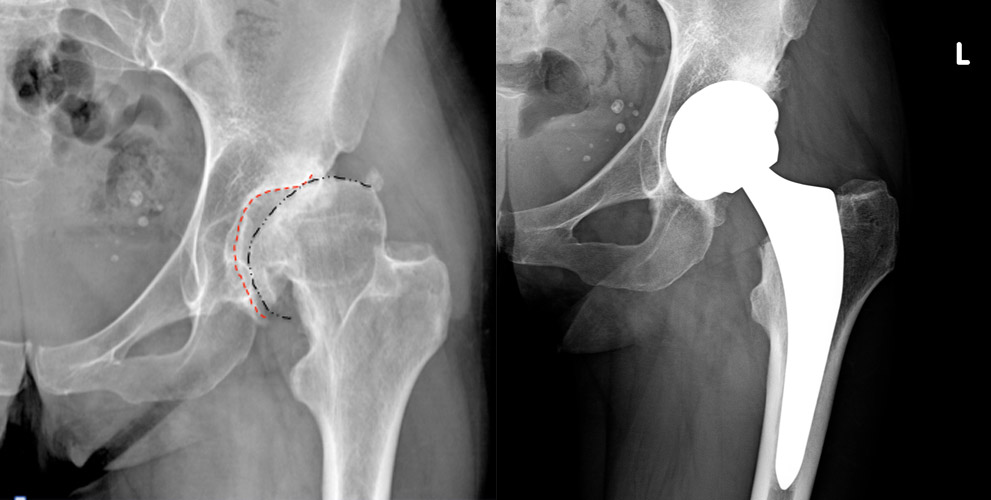

Specialista in Chirurgia Protesica Mini Invasiva Anca (incisione Mini Invasiva tradizionale e incisione “Bikini”) e Specialista in Chirurgia Protesica Ginocchio.